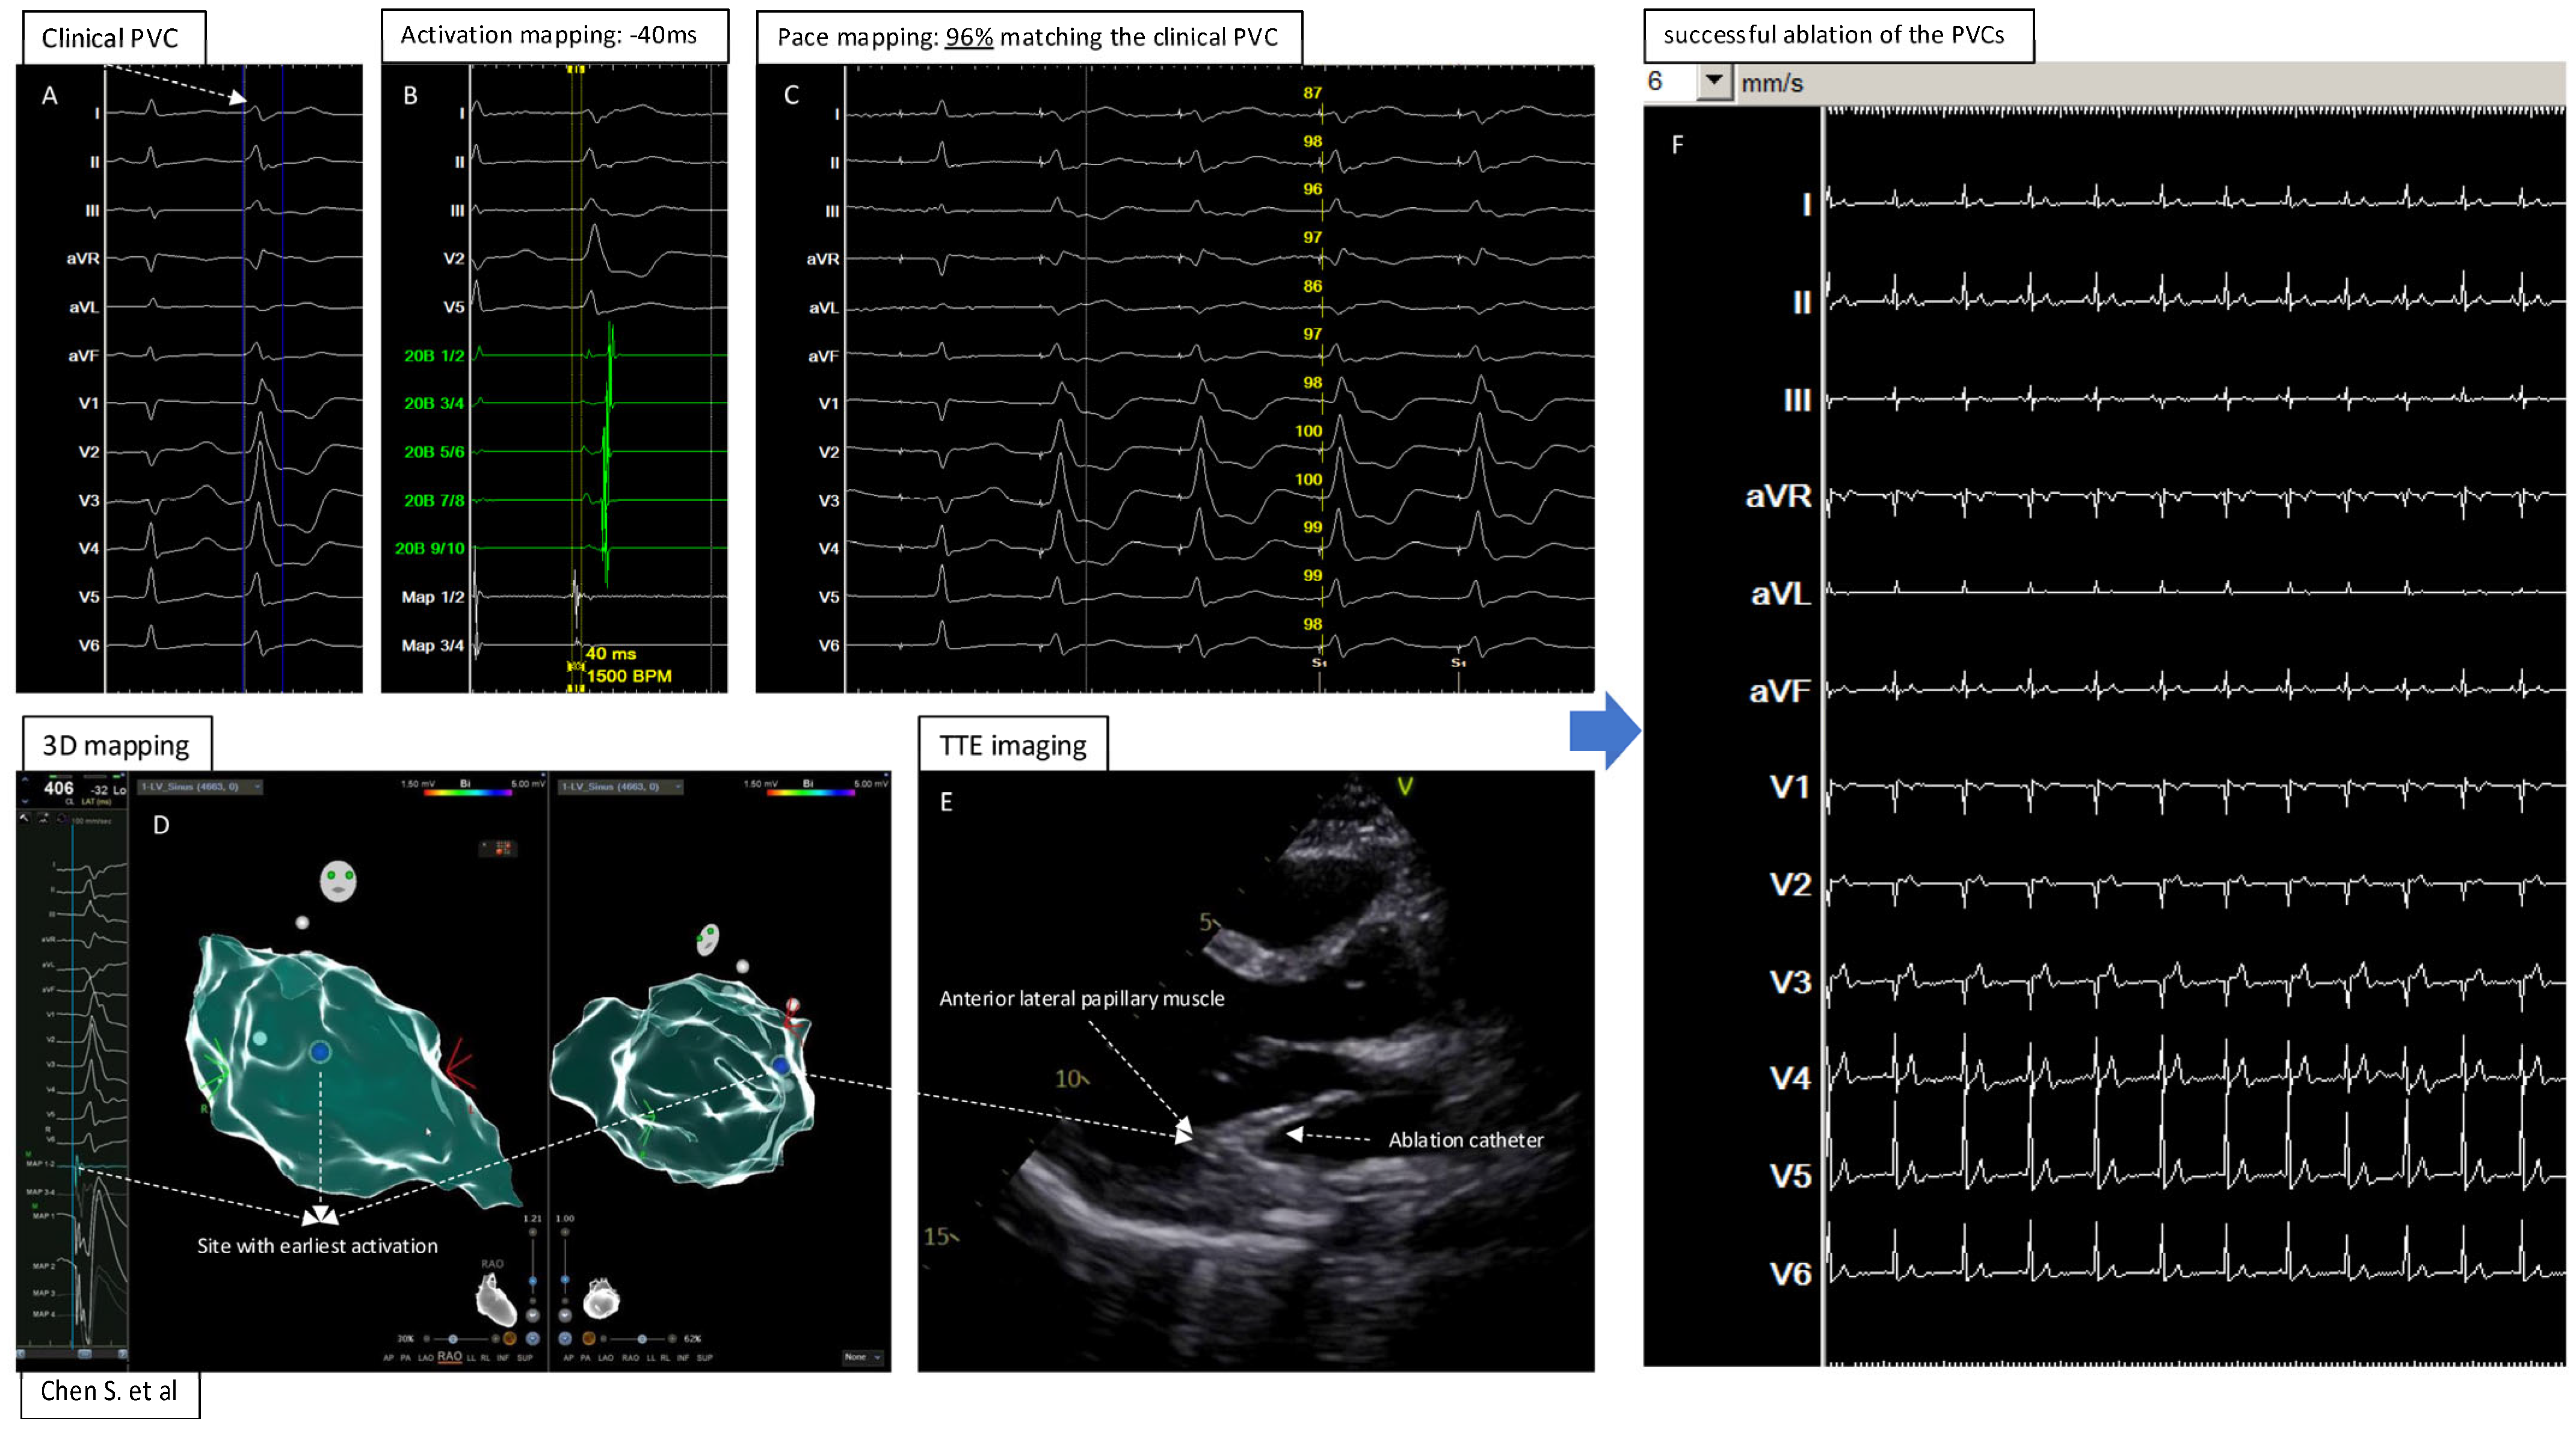

Mapping and Ablation of the PVCs